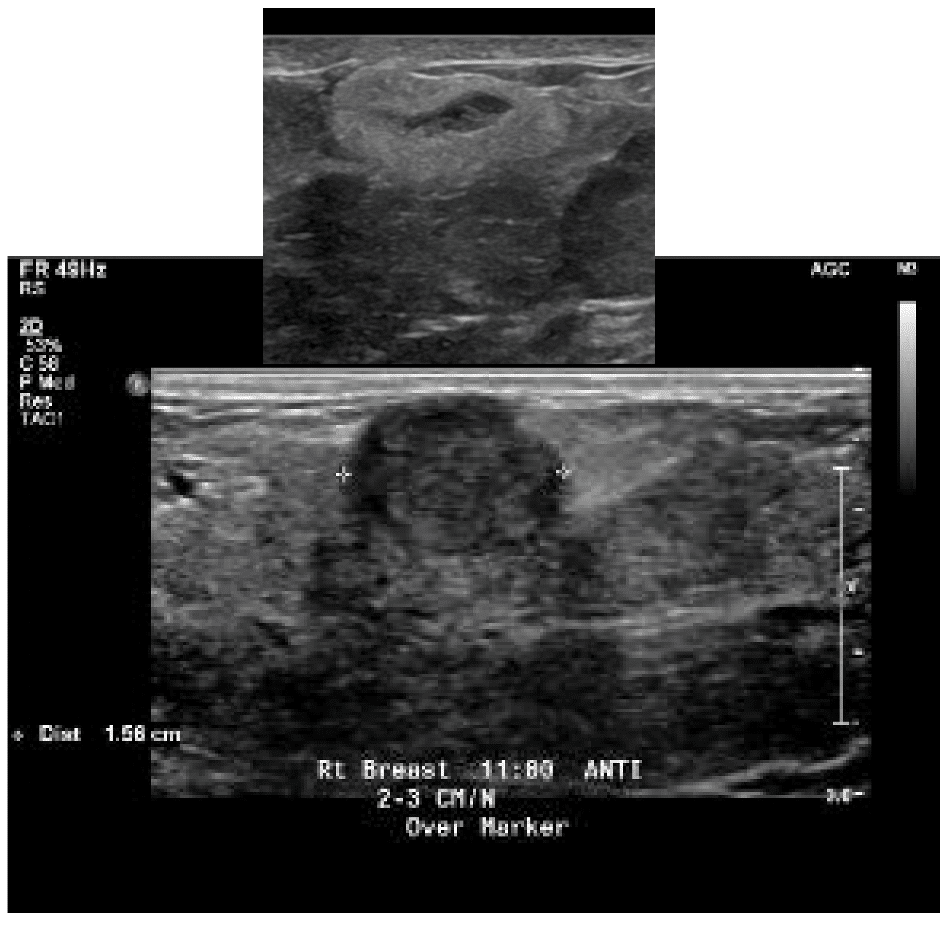

Fibroadenoma

Fibroadenomas are the most common benign (non-cancerous) growth of the breast. Fibroadenomas grow during pregnancy and lactation, and can significantly change appearance on ultrasound. Therefore, biopsy to confirm diagnosis prior to pregnancy is very important. If the lesion is not able to be confirmed fibroadenoma and is designated a non-specific fibroepithelial lesion, the patient should undergo excision to determine whether the lesion is a fibroadenoma or a phyllodes tumor (which can grow more rapidly and may not always be benign).

The video below demonstrates removal of a phyllodes lesion during lactation. There are several things to learn from this video:

- Breast imaging, breast biopsy, and breast surgery are safe during pregnancy and lactation. In fact, it would have been more ideal to remove this mass during pregnancy (before it grew and to rule out anything worrisome like a malignant phyllodes tumor). It also is far easier to operate without complication on a pregnant, rather than lactating, breast.